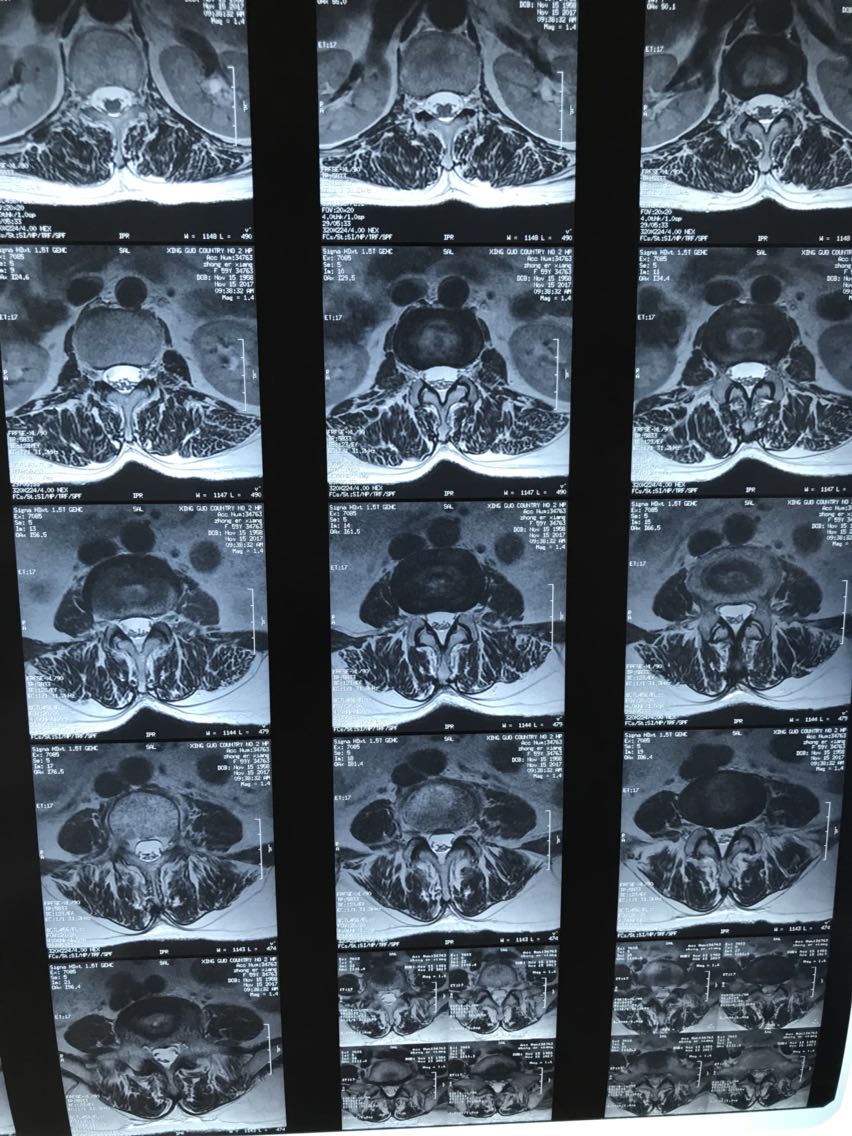

病理性骨折需要手术吗

病理性骨折